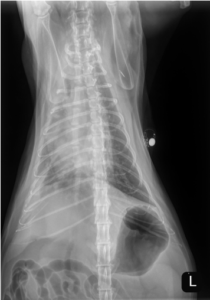

Unfortunately, the patient represented to the PVESC ER the day after discharge, for dyspnea, drooling, and frothing as well as an expiratory wheeze. On presentation he was given a 2 mg/kg dose of furosemide IM as well as butorphanol and alfaxalone for sedation to complete initial diagnostics. Thoracic radiographs on intake showed a mild cardiomegaly, moderate patchy interstitial pattern, and mild pleural fluid (see below). He was continued on 2 mg/kg furosemide IV (received two total doses approximately 4 – 6 hours apart). Later that day, an echocardiogram was performed which showed mild to moderate diffuse left ventricular concentric hypertrophy and only high normal left atrial size. The size of the left atrium was unexpected for the degree of pulmonary edema present on radiographs. At the time it was suspected that the patient likely experienced congestive heart failure secondary to fluid intolerance with underlying cardiomyopathy. Naturally occurring congestive heart failure (meaning congestive heart failure secondary to natural progression of feline cardiomyopathy) was considered less likely given the normal to minimally enlarged left atrial size (however, it could not be fully ruled out). The patient was discharged in the evening with oral medical management (furosemide, clopidogrel, and spironolactone) as he experienced significant stress in hospital and his respiratory rate and effort had improved significantly since presentation without the need for continued oxygen supplementation.